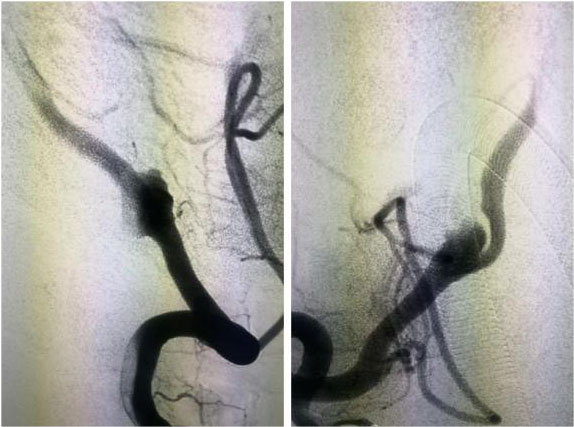

动脉瘤栓塞术:

只需要在病人大腿根部开个小切口,用一根纤细的微导管经血管抵达所要治疗的动脉瘤部位,向动脉瘤内堵塞非常精细的弹簧圈,达到很好治疗动脉瘤的目的。是微创外科的方法之一。

▲ 一位动脉瘤患者术前影像

▲ 术后,造影显示动脉瘤无显影,栓塞成功